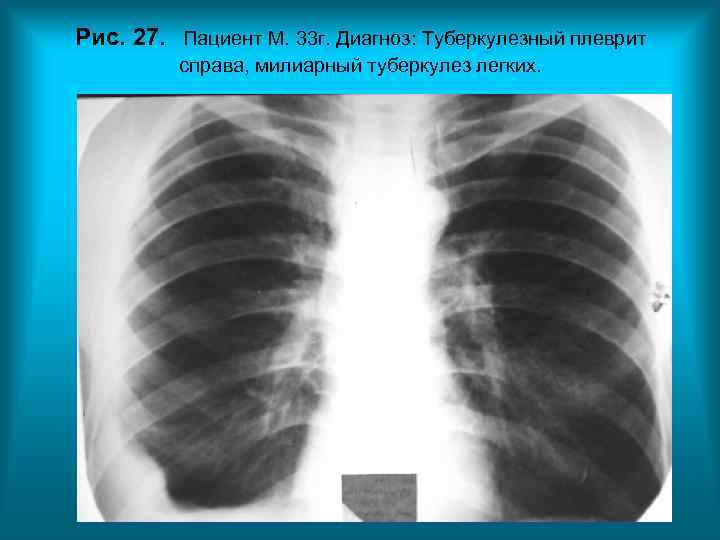

Рис. 27. Пациент М. 33 г. Диагноз: Туберкулезный плеврит справа, милиарный туберкулез легких. Н. С. Воротынцева. С. С.